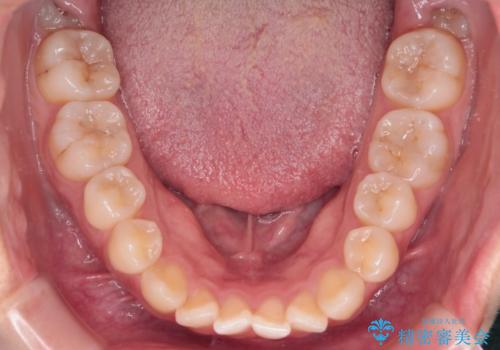

【インビザライン】前歯の凸凹を治したい

- 前歯の凸凹を主訴に来院されました。

インビザラインにて臼歯部の遠心移動を行いながら、できるだけ前歯が出ないように気を付けて治療を行っています。

遠心移動を行う必要があったので、患者様には顎間ゴムを使用していただきました。